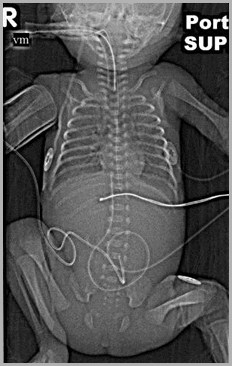

UAC at T5UVC probably in left atrium or pulmonary vein

5

UVC in left atrium

Auckland